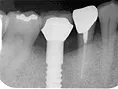

| 自費治療 インプラント |

治療前

インプラントは第二の歯とも呼ばれ 顎の骨に金属製のネジを立てて 人工の歯を取付けます 当院では高い技術と経験で対応しています ■長所 ・しっかり噛むことができる ■短所 ・禁忌症がある ・高い インプラント・くわしく |